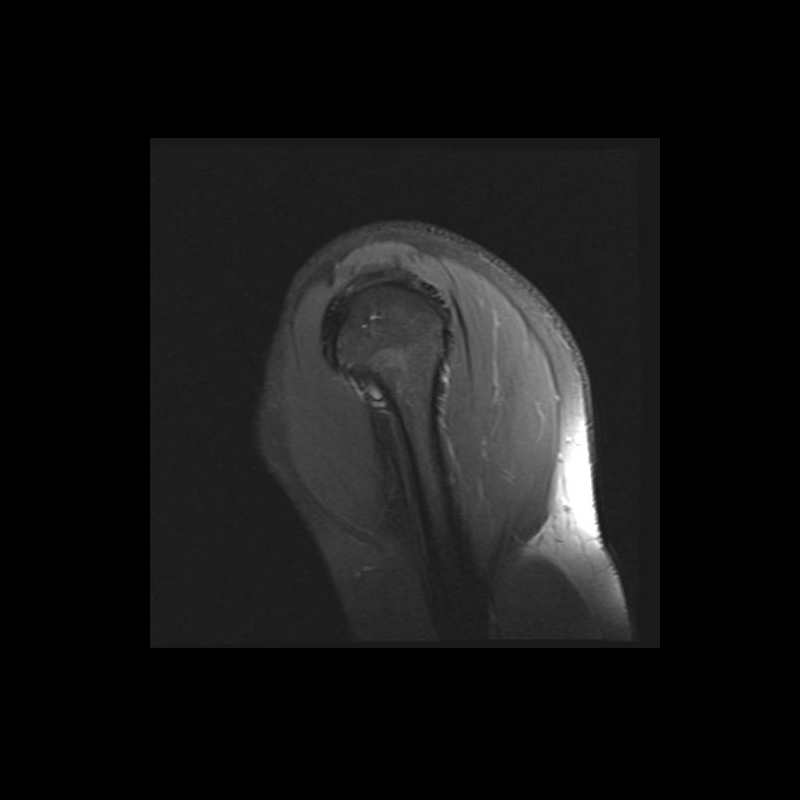

Shoulder MRI Anatomy